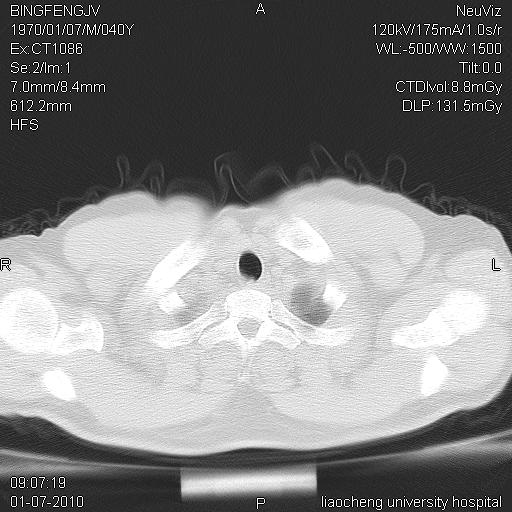

标题: CT23764B:男 40 肺部CT [打印本页]

标题: CT23764B:男 40 肺部CT

治疗2周后

炎症性病灶,继发性改变。

考虑左肺上叶近胸膜下炎症并肺气囊形成。

炎症,大部吸收。